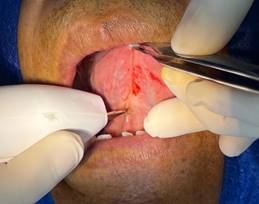

· Diéresis: Se sujetó la lengua con la ayuda de una pinza Adson con dientes, después se utilizó el electrobisturí realizando cortes lineales verticales o ligeramente convergentes hacia apical. (Figura 4)

Figura 4. Diéresis.

Elaboración: Los autores.

· Desprendimiento nítido del frenillo: Al terminar la primera fase de la diéresis se debe observar el desprendimiento nítido de la inserción del frenillo. Con este desprendimiento se intenta evitar la recidiva. (Figura 5)

Figura 5. Desprendimiento nítido del frenillo.